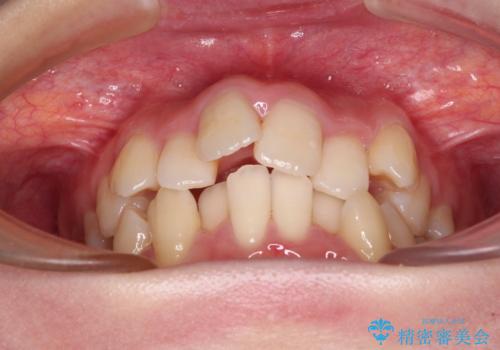

デコボコと出っ歯 抜歯矯正でスッキリとした口元に

- 上下前歯の八重歯やデコボコと、唇の閉じにくさを気にして来院された患者様です。

口元の突出感を改善するため、上下左右の第一小臼歯4本を抜歯し、ワイヤー装置にて矯正治療を行うこととしました。